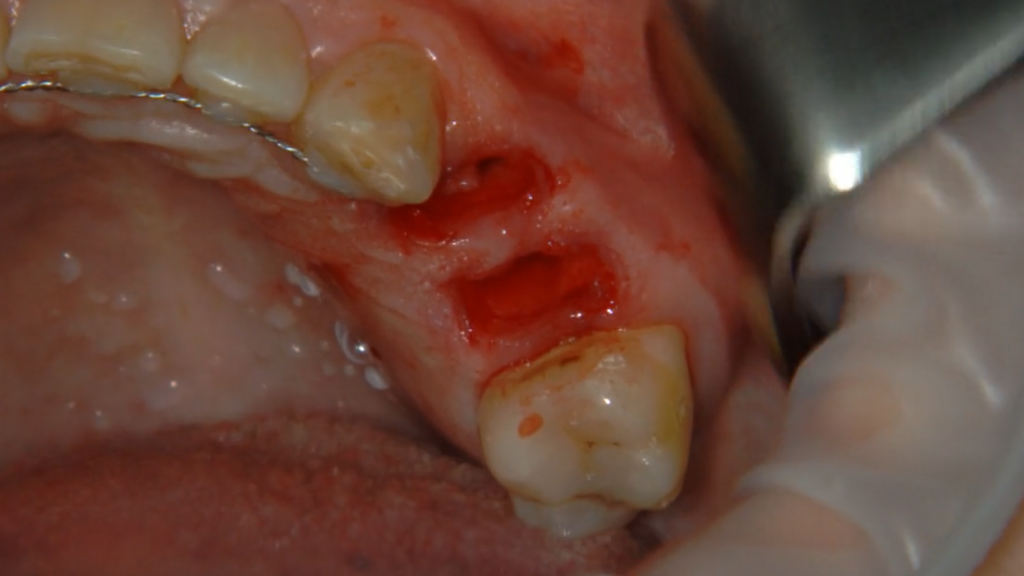

Описание клинического случая:

• Атравматичное удаление зуба 2.4, 2.5

• Одномоментная дентальная имплантация IMPRO

• Использование фибриновой мембраны Clot-PRF

• Установка временного абатмента IMPRO

• Изготовление индивидуального формирователя десны

Клинический случай Узденовой Зульфы Альбертовны